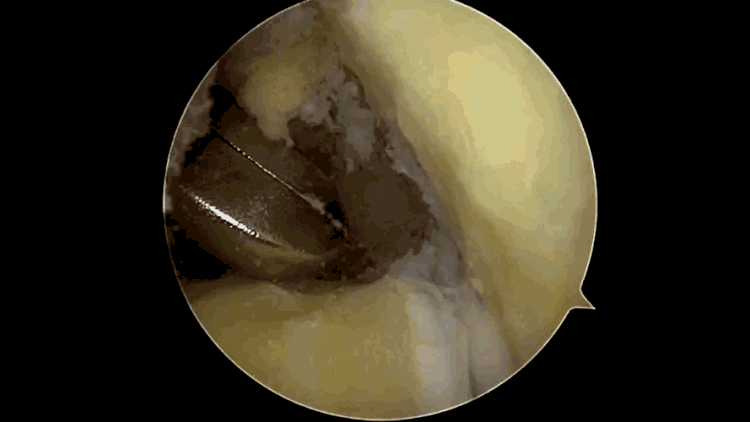

1.肘关节游离体及滑膜软骨瘤摘除手术

是肘关节镜比较简单的手术,方便快捷,安全可靠!